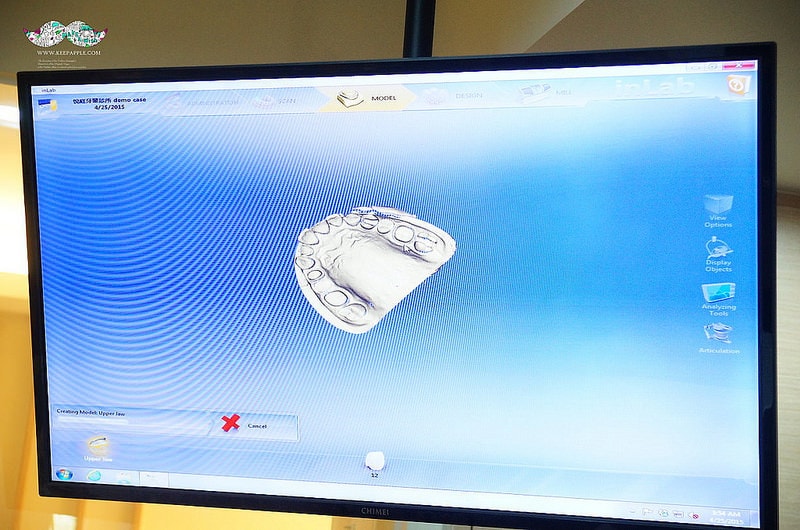

首先就是這個全彩攝影口內取像儀

這CEREC掃描機只要拿著攝像鏡頭在口中掃描

從咬合面、內側、外側各掃過一次

就可以把將病患口腔的牙齒整個模擬完成

且全裸視3D立體完整圖在短時間內就建構出來

重點是居然連小細節跟咬合都可以掃描出來真的很誇張!

鏡頭切換到數位全瓷設計研磨中心的內部

剛才用口內全彩取像儀掃描完的影像

會馬上把資料連線傳到數位全瓷設計研磨中心

可以迅速地在這邊做出牙套